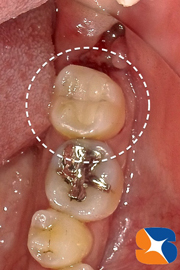

本日、2度目の来院。出血も落ち着いていたので、早速セレックを虫歯の部分をスキャン(ビデオ撮影)しました。

パソコン画面で虫歯の詰め物(オールセラミック)の設計を行いました。

無事にオールセラミックの詰め物が、抜いた親知らずの手前の歯に接着させる事が出来ました。